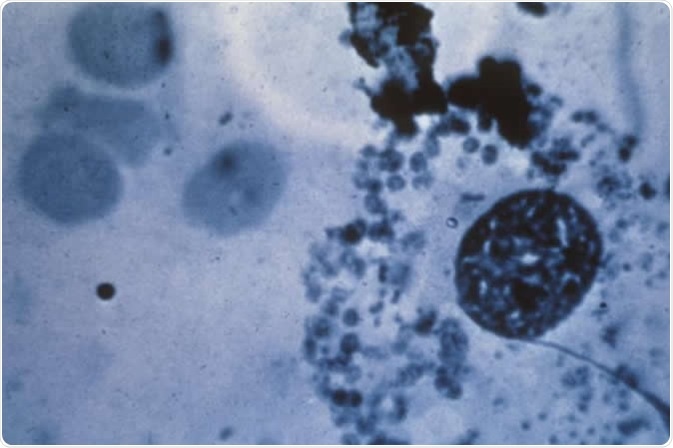

This photomicrograph reveals “Donovan bodies” in a skin sample used to diagnose granuloma inguinale.

This photomicrograph reveals “Donovan bodies” in a skin sample used to diagnose granuloma inguinale. Diagnosis of granuloma inguinale is based on the appearance of encapsulated bacilli called Donovan bodies. These are safety pin-shaped microorganisms that appear inside infected tissue cells under a microscope. Image Credit: CDC/ Richard O. Deitrick